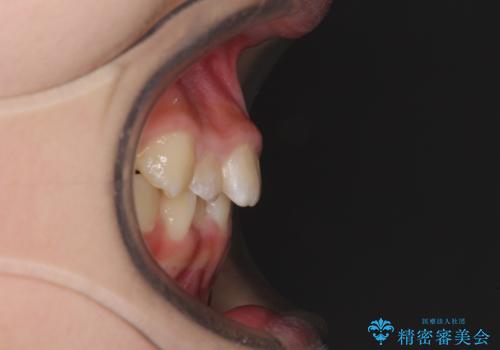

上顎骨の幅が下顎骨よりも小さいので、拡大装置により骨幅を広げて上下関係を改善し、その後インビザラインにて歯並びを整えることとしました。

上下の骨幅を改善したことで、スムーズに歯列矯正を行うことができました。